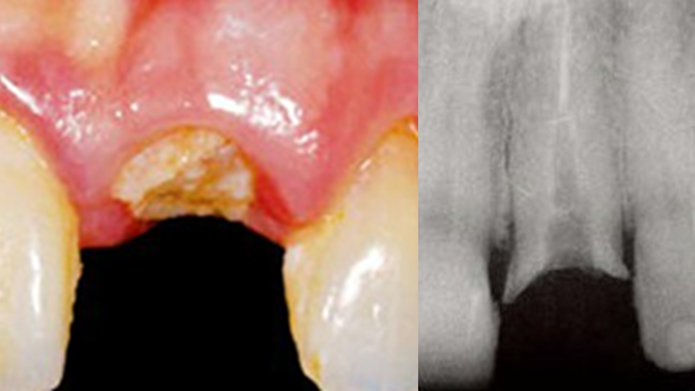

Clinical case: Replacement of fractured central incisor (#11) with immediate implant

& Root Membrane Technique

- Courtesy of Dr. Miltiadis Mitsias, Greece -

AnyRidge, Root Membrane Technique, retrospective study, long-term study, immediate implants, bone resorption, bone preservation, Dr. Miltiadis Mitsias,survival, success, maxillary anterior, single replacement

AnyRidge implant system, Root Membrane kit

The Root Membrane Technique: A retrospective clinical study with up to 10 years of follow-up./Implant Dent. 2018 Oct;27(5):564-574

https://www.ncbi.nlm.nih.gov/pubmed/30161062